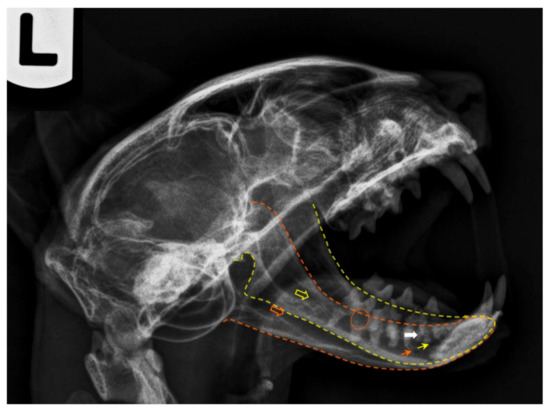

Figure 5. Postmortem radiography of a cat head, laterolateral projection (left lateral recumbency). The yellow outline corresponds to the left mandible and the orange one to the right jaw. The respective coloured empty arrows point the mandibular foramina, and the small arrows indicate the main mental foramina. The orange circle shows signs of tooth root resorption and the white arrow points evidences of a dental root fracture. Note that a plastic needle cap was used to keep the mouth open. As plastic is radiolucent, it does not interfere with the radiologic image.

The lateral projection of the feline mandible (Figure 5) is bordered ventrally by the ventral cortex and dorsally by the cusps of the premolars and molar. The area corresponding to the location of the mandibular canal, containing the neurovascular bundle (the alveolar mandibular nerve, artery and vein) appears as a radiolucent area just dorsal to the ventral cortex and ventral to the dental roots. When evaluating any tooth, the following are assessed: crown (and enamel) and pulp chamber, root and root canal, periodontal ligament space and alveolar bone. The relative radiolucent line outlining the roots (lamina lucida) is the periodontal ligament space. It is wider early in age and is typically widest at the coronal and apical one-third of the root [38]. Adjacent to this ligament space is a radiodense line (lamina dura), which is the cortical bone of the alveolus. Contiguous to it is the trabecular bone of the alveolus. The crown is covered by a more radiodense margin, which is the enamel, and the bulk is dentine, which is not as radiodense as enamel but is radiodense compared to bone. Because the cementum has nearly the same radiodensity as bone, it is not obvious radiographically. In multirooted teeth, bone should be present up to the apex of the furcation. The centre of the root is the radiolucent root canal, which houses the radicular portion of the pulp.